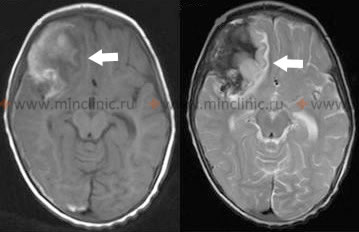

Если исследование пациента проведено в первые 48 ч после разрыва аневризмы, то при проведении магниторезонансной (МРТ) или компьютерной томографии (КТ) головного мозга без контрастирования более чем у 75% больных обнаруживают изменения, свидетельствующие о наличии сгустков крови в субарахноидальном пространстве. Количество и место нахождения крови в субарахноидальном пространстве могут помочь в определении локализации прорвавшейся аневризмы и выяснить причины первоначального неврологического дефицита. Кроме того, МРТ и КТ могут оказать помощь в прогнозе того, у кого из больных возможно развитие отсроченного неврологического дефицита, обусловленного спазмом артерий головного мозга (церебральный вазоспазм).

На первом этапе диагностики больному с подозрением на разрыв внутримозговой аневризмы проводят МРТ или КТ головного мозга без введения контрастного вещества. Контрастирование при КТ ангиографии или МРТ ангиография без внутривенного введения контраста сосудов головного мозга способны выявить изменения сосудистого русла у пациента, обнаружить аневризму или показать не предполагавшуюся у пациента артериовенозную мальформации (АВМ, ангиома, гемангиома). Если при проведении МРТ или КТ головного мозга не удаётся ни поставить диагноз субарахноидального кровоизлияния, ни выявить объёмный процесс или обструктивную гидроцефалию, следует произвести люмбальную пункцию с целью установить наличие крови в субарахноидальном пространстве.

Если у больного диагноз субарахноидального кровоизлияния, обусловленного разрывом мешковидной аневризмы, установлен, то проведение ангиографии откладывается до момента хирургического вмешательства. Церебральную ангиографию обычно проводят непосредственно перед операцией для уточнения локализации и характеристики анатомии аневризмы, а также для подтверждения наличия или отсутствия очагового спазма артерий мозга (церебральный вазоспазм). Если присутствие крови в веществе мозга или субарахноидальном пространстве над большим полушарием головного мозга, а не в базальных цистернах заставляет предполагать артериовенозную мальформацию (АВМ, ангиому, гемангиому) или микотическую аневризму, то ангиографическое исследование должно быть осуществлено немедленно. Другим показанием к выполнению неотложной ангиографии у пациента является внутримозговая гематома, появившаяся в результате разрыва аневризмы, которая при развитии отёка мозга может послужить поводом для экстренного нейрохирургического её удаления в связи с опасностью вклинения височных долей в намёт мозжечка, смещение ствола мозга и т.д.. Обязательным условием в ходе подготовки к операции является определение точной локализации и анатомии разорвавшейся аневризмы сосуда мозга.

Технически выполнение удаление локальных гематом и выключение разорвавшихся аневризмы клипсами не сложно, но некоторые кровяные сгустки слишком велики по объёму, чтобы их можно было удалить полностью и без последствий для пациента. Поэтому время нейрохирургической операции в случае разрыва аневризмы артерии мозга выбирают индивидуально для каждого больного. Если на магниторезонансной (МРТ) или компьютерной томографии (КТ) головного мозга у пациента в субарахноидальном пространстве не обнаруживают больших сгустков крови или если потенциально опасный сгусток можно мягко и эффективно извлечь, то возможно раннее нейрохирургическое вмешательство.